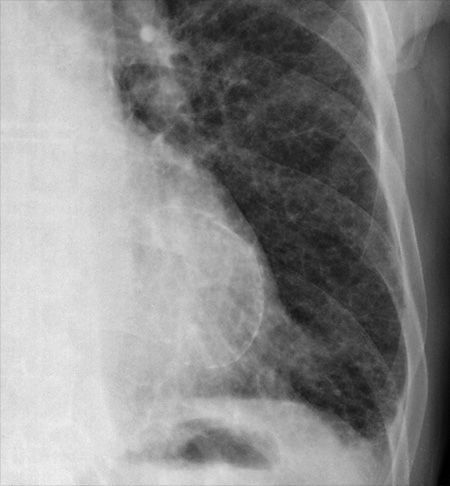

X-RAY QUIZ: Which finding is present on this image?

B: Sail sign

C: Meniscus sign

Start Quiz bit.ly/36i1txn